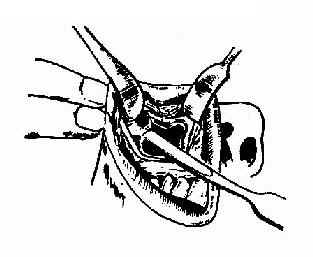

开放性骨折可自创口伸入钝钩或剥离器将骨片复位,彻底清创,去除异物及碎屑,并于下鼻道前下凿一对孔通入上颌窦,填入碘仿纱条,自对孔引出,缝合伤口。3~5d后自鼻腔抽出纱条。闭合性前壁塌陷骨折,颧弓或眶底骨折者,可自颧弓上或眶下作切口,进行骨折复位。也可按照上颌窦根治手术作切口进入窦内,用钝性器械将骨折复位,清理窦内异物及碎骨片,自下鼻道行对孔引流,窦内填入碘仿纱条固定下陷的骨折。3~5d后,自前鼻孔内抽出纱条(图13-7,13-8)。

图13-7 颧骨骨折经上颌窦复位法